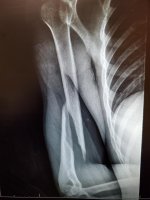

After throwing a 88 mph pitch